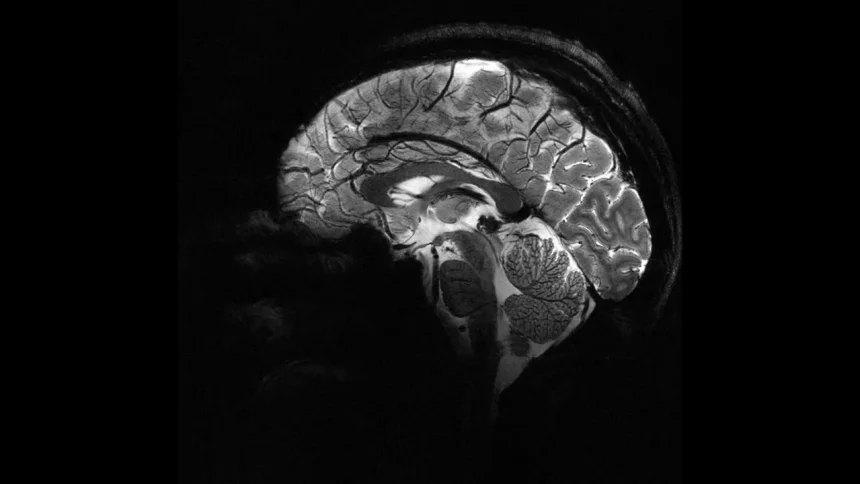

Epilepsiya müxtəlif səbəblərlə ortaya çıxa bilər, lakin halların təxminən 30 faizi beyindəki struktur anomaliyalarla bağlıdır. Bu lezyonların bir qismi beynin qıvrımlarının dərinliklərində gizləndiyi üçün MRT görüntülərində tez-tez gözdən qaçırılır. Süni intellekt isə bu incə detalları taparaq həkimlərə əlavə dəstək verir.

Araşdırmada kortikal displazi və fokal epilepsiya xəstələri üzərində testlər aparılıb. Əvvəllər MRT nəticələri “normal” göstərilən uşaqların 80 faizində əslində gizli lezyonların olduğu müəyyən edilib.

Süni intellekt həm MRT, həm də PET müayinələrini birgə analiz edərək bir qrupda 94 faiz, digərində isə 91 faiz dəqiqlik əldə edib. İlk test qrupundakı 17 uşağın 12-si əməliyyat olunub və 11-i artıq tutmasız yaşayır.